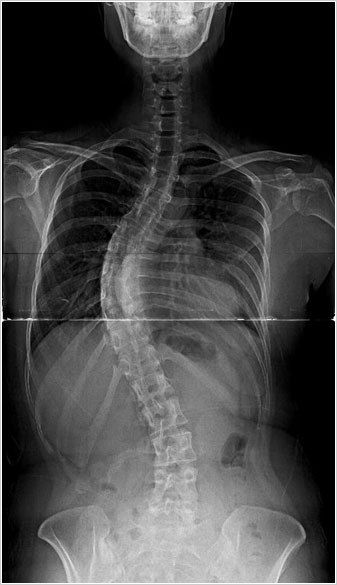

Á¤Áß¾ÓÀÇ ÃàÀ¸·ÎºÎÅÍ Ã´Ãß°¡ Ãø¹æÀ¸·Î ¸¸°î ¶Ç´Â ÆíÀ§µÇ¾î ÀÖ´Â

±âÇüÀûÀÎ »óŸ¦ ¸»ÇÕ´Ï´Ù. |

ôÃß°¡ ÀüÇüÀûÀ¸·Î ÇÑ ÂÊ ¹æÇâÀ¸·Î

ÈÖ¾îÁ³´Ù°¡ ´Ù½Ã ´Ù¸¥ ÂÊ ¹æÇâÀ¸·Î ÈÖ¾îÁø °ÍÀ» °üÂûÇÒ ¼ö ÀÖÀ¸¸ç º¸´Ù ÈçÇϰԴ S

ÀÚ ¸ð¾çÀ¸·Î ¾çÂÊ ¹æÇâÀÇ ¸¸°îÀÌ ±ÕÇüÀ» ÀÌ·ç°í ÀÖ´Â °æ¿ì°¡ ¸¹½À´Ï´Ù. ±× ¿Ü¿¡µµ ´ÙÀ½°ú

°°Àº ¡Èĸ¦ °üÂûÇÒ ¼ö ÀÖ½À´Ï´Ù.

û¼Ò³â±â Ư¹ß¼º ôÃßÃø¸¸Áõ : 20¼¼/¿©ÀÚ